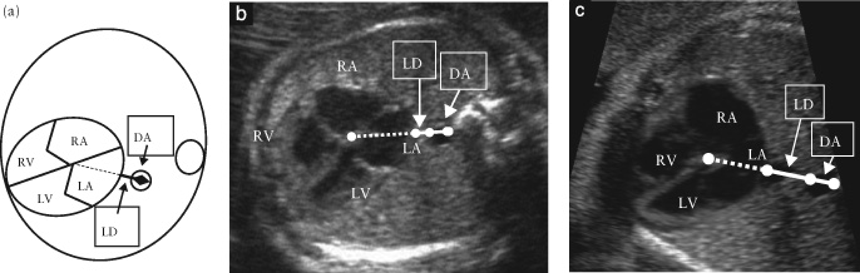

そして2014年にKawazuらは,左房–下行大動脈間距離を下行大動脈径で除した値をPLAS indexとし,isolated TAPVCの胎児診断に有用と報告した20).具体的には,胎児isolated TAPVC8例と正常胎児101例において,PLAS index(=左房–下行大動脈間距離(LD)/下行大動脈径(DA))(Fig. 3)を比較したところ,TAPVC症例は有意に高値であり(p<0.0001),PLAS indexが1.27以上であるとTAPVCが疑わしいと報告した(感度100%,特異度99%).2016年にはAkkurtらが,在胎20~24週の正常胎児165例においてPLAS indexの計測を行い,その値が0.65+/−0.13と低値であったことと在胎週数による変動がなかったことを報告しており31),Isolated TAPVCの胎児診断に期待される指標と考えられる.ただ一方でPLAS index低値であった偽陰性例の報告もある32)ことから,単独で使用するのではなく他の指標も合わせて診断することが必要かもしれない.